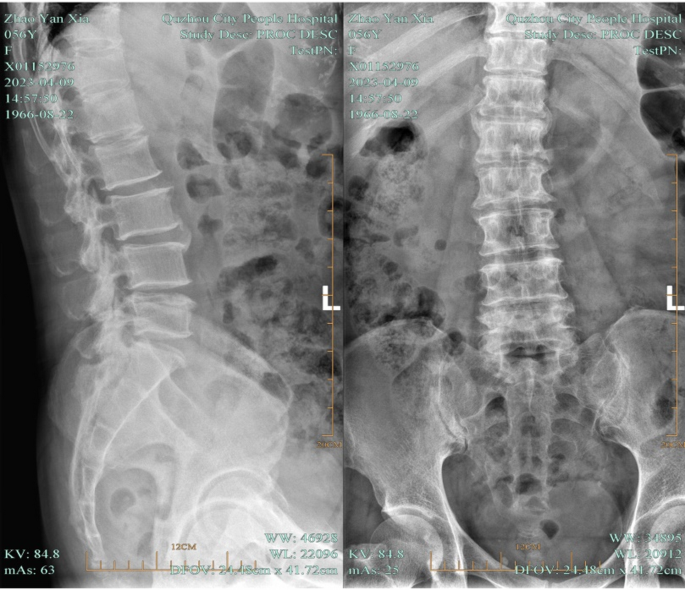

Patients in the experimental group received UBE-assisted interbody fusion surgery. After being given general anesthesia, the patient was positioned prone. The surgical site was identified using C-arm fluoroscopy by projecting the pedicle’s body surface on both sides of the waists 4 and 5. Standard cleaning and sterile sheeting were then carried out. Based on the indicated points, lateral puncture of the pedicle was done. Fluoroscopic examination of the puncture needle’s location during the procedure was necessary to determine whether it was at the vertebral arch’s pedicle. Following confirmation, the guide wire could be placed. The operation and observation channels could be built by making a double incision along the left side to introduce the skin expander. It was necessary to insert a 30° arthroscope into the observation channel after connecting the light source. Following a clean removal of the surrounding soft tissue in the work channel, adequate hemostasis was achieved with the use of a radiofrequency knife. The field of vision was exposed to the lower edge of the L4 vertebral plate and the higher edge of the L5 vertebral plate. To expose the dura mater and nerve roots in the visual field, the lumbar 4 lamina was removed from the ligamentum flavum insertion point, the upper edge of the lumbar 5 lamina and part of the facet joints of the lumbar 4/5 were removed, and the ligamentum flavum was also removed. Subsequently, protruding lumbar 4/5 intervertebral discs, as well as compressed posterior dura mater and nerve roots could be observed. The nerve roots were pulled apart using nerve stripping ions. The intervertebral disc was removed. The intervertebral space was processed to the upper and lower endplates. The bone graft bed was prepared. The protruding nucleus pulposus was retrieved with nucleus pulposus forceps. Hemostasis and intervertebral disc ablation were carried out with a radiofrequency knife, and the endplate was scraped off. After the intervertebral space was processed, the polyetheretherketone (PEEK) Cage was implanted. The size of the cage was selected according to the height (10–12 mm) and width (16–18 mm) of the intervertebral space measured by CT before operation. The cage was built with autologous bone, and the cage was high in anterior and low in posterior (sagittal lordosis Angle 5°) to maintain the physiological lordosis of the lumbar spine. Radiofrequency ablation hemostasis could be carried out once more when the nerve root had relaxed and the dura mater pulsation was found to be normal. After implanting autologous bone particles into the patient’s intervertebral space, an interbody fusion cage made of matched autologous bone was put in place. The arthroscopy could be removed once the fusion device was properly positioned during the fluoroscopy. The pedicle screw was then screwed along the guide wire, the round rod was positioned, and the screw plug was tightened and secured. The instruments and dressings could be counted once the C-arm fluoroscopy had confirmed the internal fixture’s position and proper length. A drainage tube could be inserted once it was determined that no mistakes had been made and the patient’s incision was not actively bleeding. Disinfection was performed again, and the incision was sutured. Patients in both groups were followed up for 3 months. The operation diagram was shown in Fig. 3. Lumbar spine images before and after surgery were shown in Figs. 4 and 5.

Images of the lumbar spine before surgery in a patient with LDH.